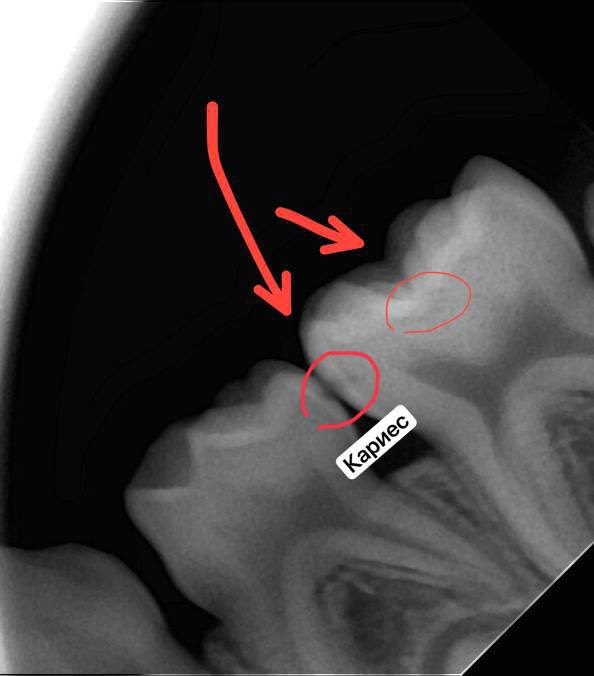

✔️увидят самые начальные стадии разрушения зубов.

✔️смогут диагностировать периодонтит, пародонтит, абсцесс и тд.

✔️детям могут диагностировать наличие или отсутствие зачатка постоянного зуба, различные аномалии развития.